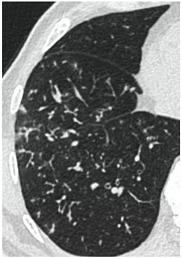

КТ имеет высокую чувствительность в выявлении изменений в легких, характерных для COVID-19. Применение КТ целесообразно для первичной оценки состояния ОГК у пациентов с тяжелыми прогрессирующими формами заболевания, а также для дифференциальной диагностики выявленных изменений и оценки динамики процесса. КТ позволяет выявить характерные изменения в легких у пациентов с COVID-19 еще до появления положительных лабораторных тестов на инфекцию с помощью МАНК. В то же время, КТ выявляет изменения легких у значительного числа пациентов с бессимптомной и легкой формами заболевания, которым не требуется госпитализация. Результаты КТ в этих случаях не влияют на тактику лечения и прогноз заболевания при наличии лабораторного подтверждения COVID-19. Поэтому массовое применение КТ для скрининга асимптомных и легких форм болезни не рекомендуется.

2. Наличие клинических проявлений, указанных в п. 1, в сочетании с характерными изменениями в легких по данным компьютерной томографии (КТ) (см. Приложение 1 настоящих рекомендаций) вне зависимости от результатов однократного лабораторного исследования на наличие РНК SARS-CoV-2 и эпидемиологического анамнеза.

- Изменения при КТ (рентгенографии), типичные для вирусного поражения (объем поражения минимальный или средний; КТ 1-2)

- Изменения в легких при КТ (рентгенографии), типичные для вирусного поражения (объем поражения значительный или субтотальный; КТ 3-4)

- Изменения в легких при КТ (рентгенографии), типичные для вирусного поражения критической степени (объем поражения значительный или субтотальный; КТ 4) или картина ОРДС.